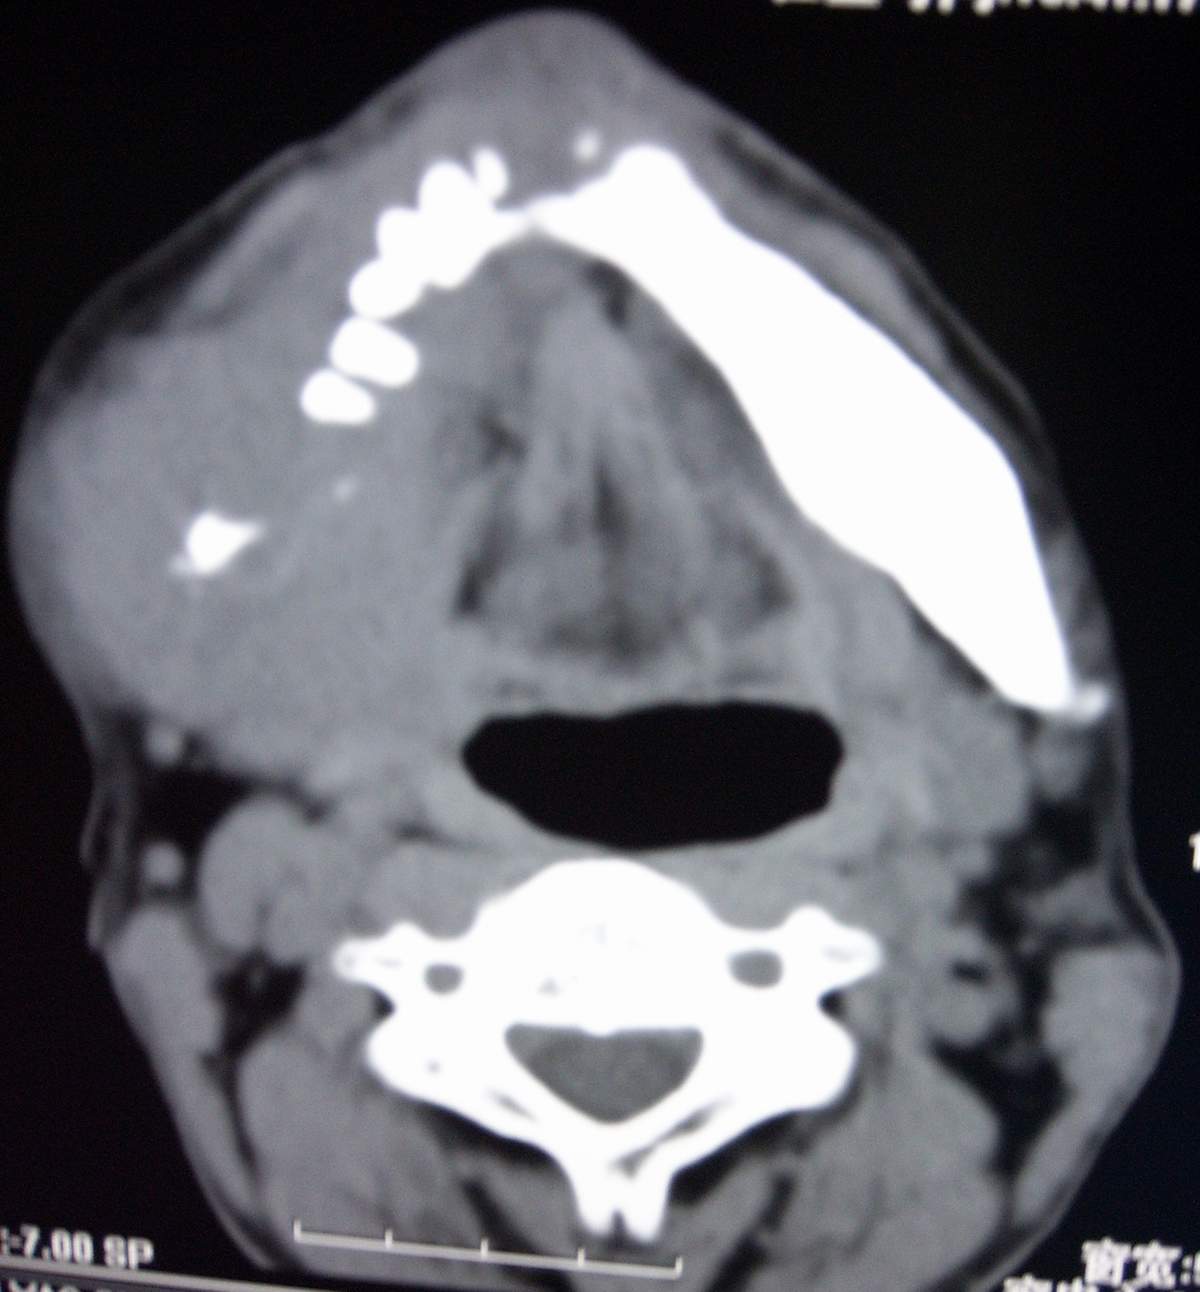

男,54岁,右下颌肿痛1月余。

右下颌骨溶骨性破坏,并见软组织形成。应考虑恶性肿瘤或转移瘤。

考虑右下颌骨转移瘤或原发恶性肿瘤,右颈部淋巴结转移.

右侧下颌骨水平部及升支呈溶骨性破坏,无明显膨胀,周围见软组织肿块。

考虑:右侧下颌骨恶性肿瘤或转移瘤。

右下颌骨恶性骨肿瘤伴右颈部淋巴结转移。

右下颌骨溶骨性破坏,代之以团块状软组织影,内有斑片状瘤骨,边缘骨质有少量骨膜反应,考虑:右下颌骨骨肉瘤。期待病理。